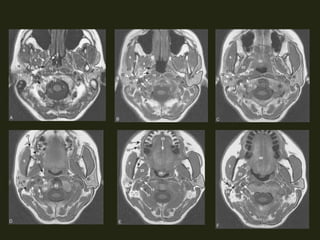

Tc5 naso orofaringe